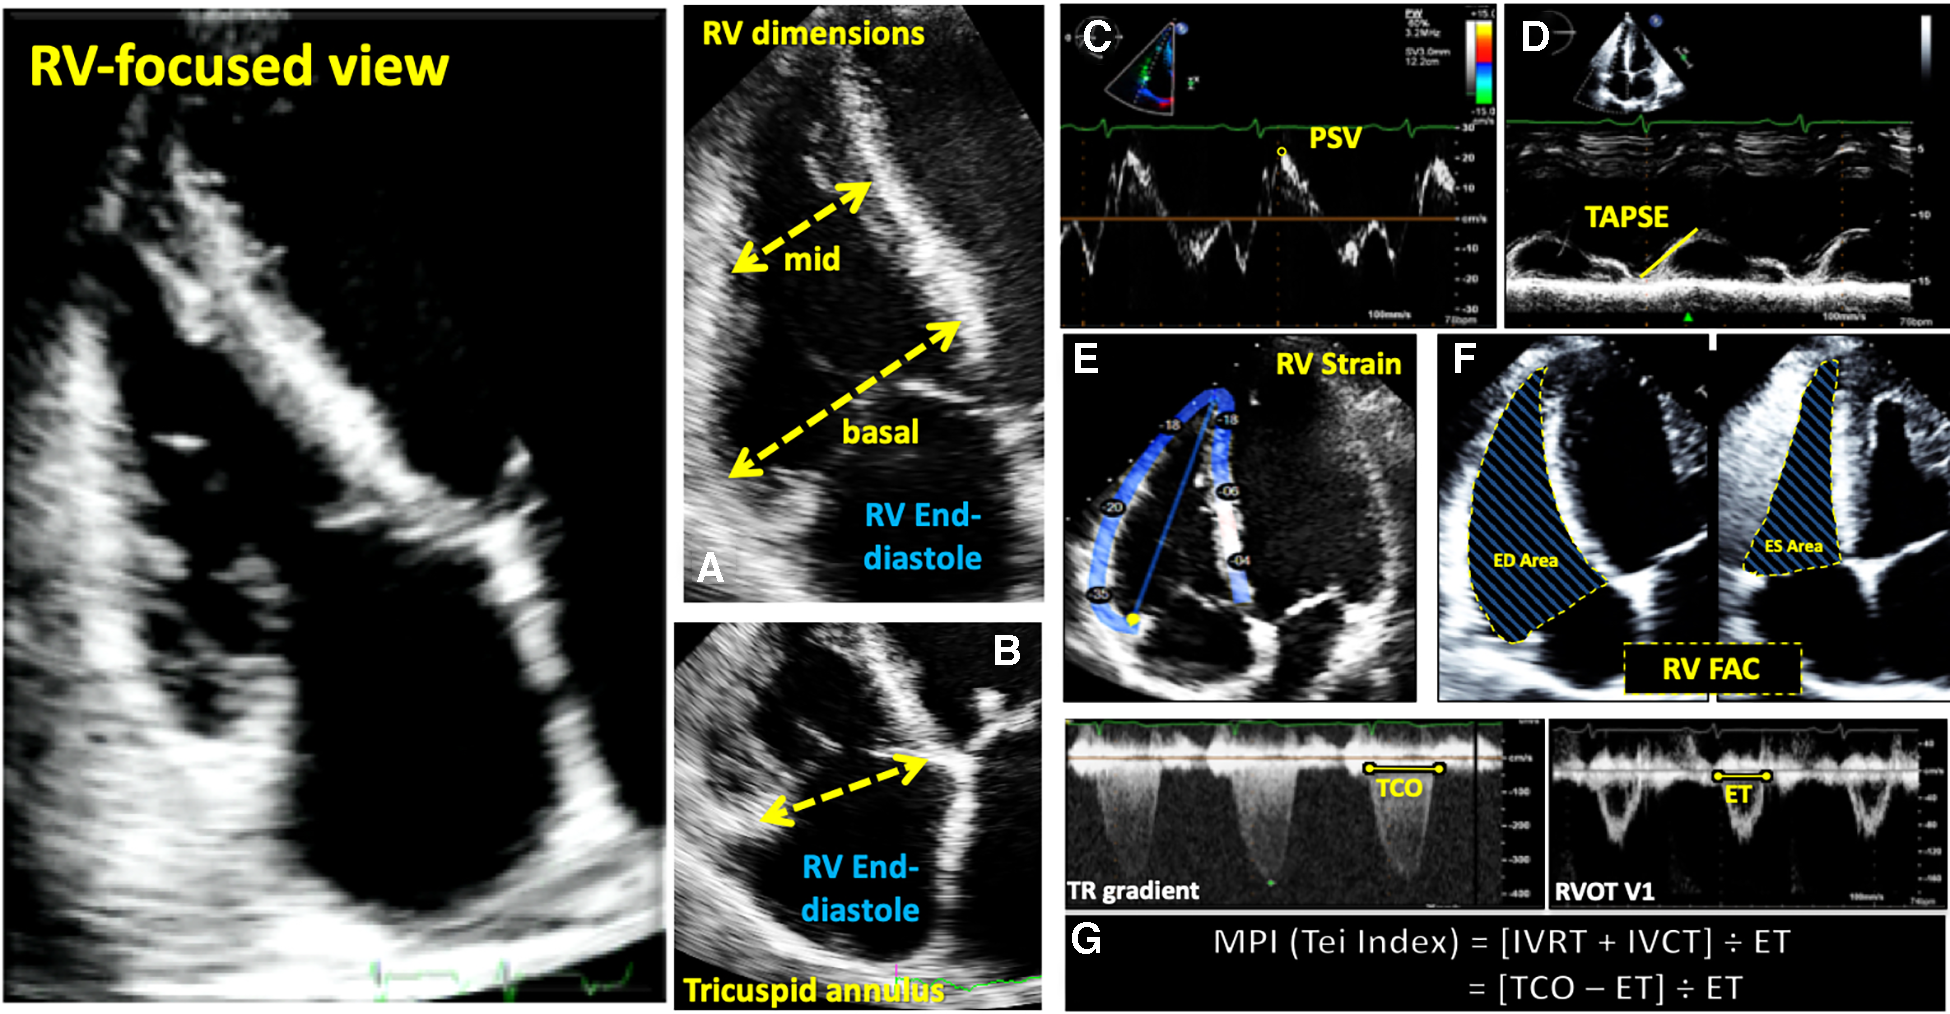

Figure 3

Guideline-recommended right ventricular size and function assessment. All measurements are performed in the RV focused apical 4-chamber view (far left panel). (A) RV mid-ventricular and basal dimensions obtained at end-diastole in the RV-focused view; (B) tricuspid annulus diameter obtained at end-diastole starting at the hinge-point of the non-septal TV leaflet and ending at hinge-point of the septal TV leaflet; (C) depiction of doppler-derived tricuspid lateral annular systolic velocity (S’) or peak systolic velocity (PSV); (D) m-mode is used to measure longitudinal displacement of the lateral tricuspid annulus in systole to yield tricuspid annular systolic excursion (TAPSE); (E) region of interest used to guide free-wall and global RV strain assessment; (F) RV areas obtained at end-diastole and end-systole to compute fractional area change; (G) Calculation of the myocardial performance index (MPI) defined as the sum of isovolumic contraction time the (IVCT) and isovolumic relaxation time (IVRT) divided by ejection time (ET) obtained from the right ventricular outflow tract initial velocity (RVOT V1). The sum of IVCT and IVRT is equal to the difference between the interval from cessation to onset of the tricuspid inflow (TCO) and ET.

Evaluation of RV systolic function on 2DE involves the integration of multiple parameters, of which the most commonly used include tricuspid annular systolic excursion (TAPSE), tissue Doppler-derived tricuspid lateral annular systolic velocity (S'), fractional area change (FAC), free-wall and four-chamber (free-wall + septal) longitudinal strain (FWS and 4CHLS respectively), and myocardial performance index (MPI) (7). Indeed, utilization of a single, global assessment of function is hindered by the complex mechanism of RV contraction that is unique from the left ventricle. In comparison to the left ventricle, the RV wall is thinner and composed of two muscular layers with longitudinally oriented myocytes in the sub-endocardium and circumferentially oriented myocytes in the sub-epicardial layer. Together, these layers contribute to RV contraction by respectively drawing the tricuspid annulus towards the apex and inwardly moving the free wall (2). Given that there is not one single accepted method for RV quantification, qualitative interpretation is often also used in clinical practice, characterizing dysfunction as mild, moderate, or severe despite poor sensitivity and notable interobserver variability (9). Routine metrics such as TAPSE and S' have demonstrated modest agreement with global RV systolic function obtained by CMR (10). These measures predominantly assess longitudinal excursion of the RV free-wall and thereby omit the contribution of other determinants of RV function. In many instances, longitudinal excursion is the most important determinant of systolic RV function. However, altered contraction mechanics and adverse remodeling in various disease states may result in under- or over-estimation of function using these methods such as in the setting of some types of pulmonary hypertension, post-cardiac surgery where systolic motion is concentrated in the transverse plane, or significant tricuspid regurgitation (TR) which produces exaggerated motion of the base (2). FAC provides a percentage estimate of global function, improving the correlation with CMR but it is highly dependent on identifying a suitable tomographic view that avoids cavity foreshortening. This limitation results in poor reproducibility. Additionally, since FAC is measured in the RV focused view, it excludes much of the RV body as well as the RV outflow tract which in itself contributes to 25%–30% of the RV volume (3, 7). Similar to FAC, FWS, a measure of myocardial shortening in the longitudinal plane, fails to incorporate the RV outflow tract and focuses on longitudinal deformation. Unlike TAPSE and RV S', FWS incorporates the entire RV free wall (or free and septal walls in the case of 4CHLS), and therefore correlates better with CMR measurements than either TAPSE or RV S' (11). Finally, MPI, or Tei index, defined as the sum of RV iso-volumetric contraction and relaxation times divided by the RV ejection time, has the ability to account for both systolic and diastolic components of RV function; however, situations such as tachycardia, elevated right atrial pressures, atrial fibrillation, and conduction system disorders prevent its consistent use (2). Overall, conventional 2D parameters (Figure 3) necessitate leveraging limited sections of the RV endocardial surface to extrapolate global function, which may subject these measures to inaccuracies. See Table 1 for an overview of advantages and disadvantages of each 2D parameter.